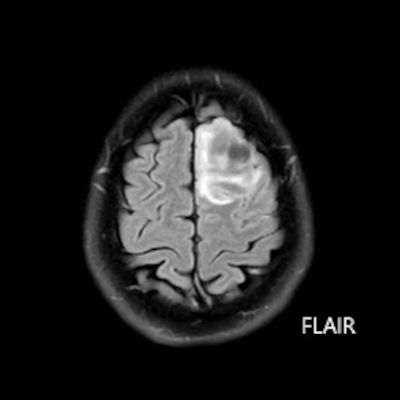

- Sol frontal kortikal-subkortikal yerleşimli aksiyel T2A görüntüde hiperintens sinyal özelliği gösteren (oklar) ve FLAIR görüntüde sinyali ağırlıklı olarak baskılanan (oklar) kitlesel lezyon izleniyor. Lezyon T1A görüntüde hipointens olup post-kontrast T1A görüntüde bu düzeyde patolojik kontrastlanma izlenmiyor (oklar).

- FLAIR’de T2’ye benzer şekilde hiperintens görünür. Ancak T2–FLAIR mismatch bulgusu, bu tümör tipi için oldukça karakteristiktir.

- T2–FLAIR mismatch bulgusu, T2AG’de homojen hiperintensite ile FLAIR görüntüde santral sinyal baskılanmasının ve çevrede hiperintens halka görünümünün bulunduğu bir fenomendir. Bu bulgu, özellikle IDH-mutant, 1p/19q kodelesyonu olmayan astrositomları tanımlamada oldukça özgül bir biomarker olarak literatürde vurgulanmıştır. Ayırıcı tanıda akla gelmesi gereken oligodendrogliomlarda T2/FLAIR mismatch bulgusu genellikle görülmez.

- Olgumuzda T2-FLAIR mismatch bulgusu mevcut olup, opere edilmiş ve tanısı histopatolojik olarak konulmuştur.